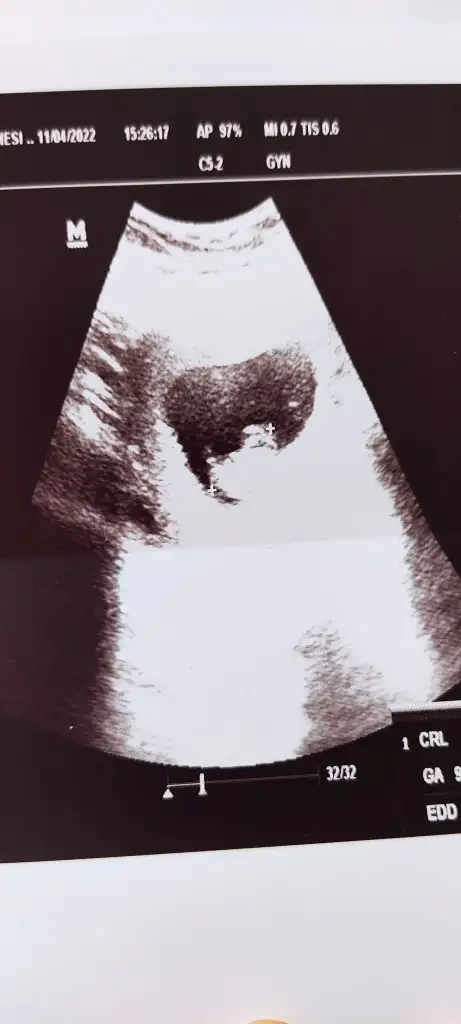

Slm canım nasılsın bakalım 🥰 9+1 deyiz tekrar bakıp yorumlayabilir misin rica etsem 🥰

• IMG_20220412_155700.webp

IMG_20220412_155700.webp

17,8 KB · Görüntüleme: 69

• IMG_20220412_155652.webp

IMG_20220412_155652.webp

17,3 KB · Görüntüleme: 66

Sana önceden ne dedim. kuzum bilmiyorum ama burda kız görünüyor

6 buçuk haftalık tık erkek demiştin kuzum şuan 9 haftamdayım Allah'ın izniyle sağlıklı olsun evlatlarımız gerisi önemli değil eşim kız istiyor ben erkek istiyorum bakalım hayırlısı olsun 🙏 dur eskisinide atiyim hatta şimdi ikisini karşılaştır istersen 🥰

senin 6. hafta görüntüsü vajinal mı kuzum eğer vajinalsa iki görüntüde kız diyor eğer değilse benim gibi bebek yer değiştirmiş